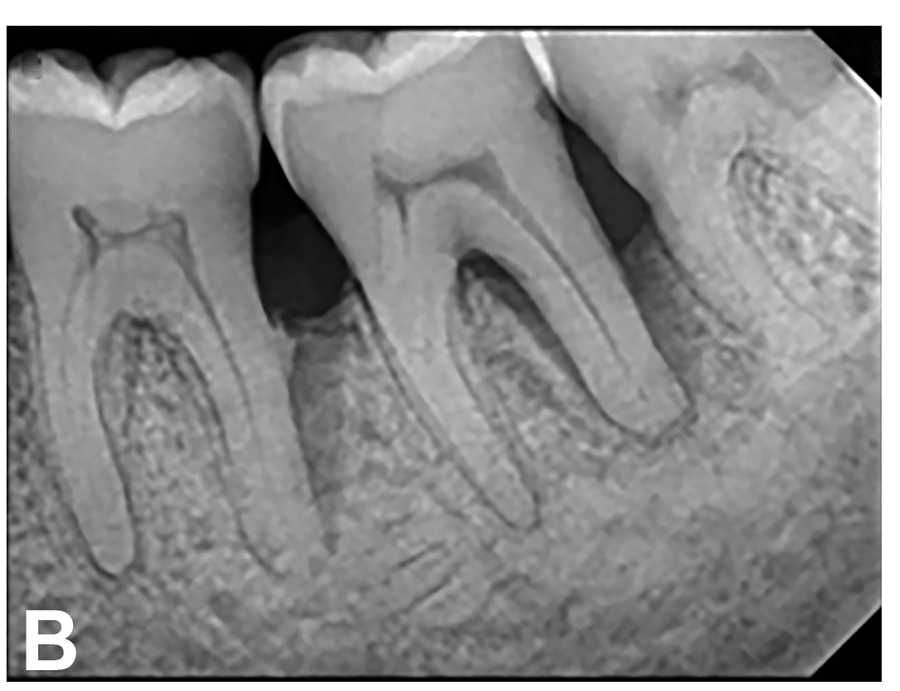

(6.) Initial periapical radiograph taken on November 15, 2015, showing infrabony defect approaching the apex of the distal root of tooth No. 19, on which there was a calcified mass (hypercementosis) and evidence of furcal bone loss. The entire distal root of tooth No. 18 appeared to have no bone support, and a small arrested carious lesion was noted on the distal crown of tooth No. 18. Teeth Nos. 17 and 18 were initially given a hopeless prognosis and slated for extraction.

Figure 6

(7.) Progressive improvement in bone quality, quantity, and morphology during each time period, especially in the furcation area of tooth No. 18, which shows a noticeable narrowing of the width of the bony defects, slight apical resorption of the distal root of tooth No. 18, and the encasing of residual cementum on the distal root of No. 19 by new bone formation. Periapical radiographs were taken of teeth Nos. 17, 18, and 19 on June 25, 2016, January 28, 2017, August 23, 2019, and September 4, 2020, respectively, the final of which was taken after almost 5 years post-initial scaling and root planing and alternating supportive periodontal maintenance.

Figure 7

The patient's periodontal disease improved with initial nonsurgical periodontal therapy that involved scaling and root planing. This initial treatment was followed by only SPT every 3 months. Despite treatment, residual deep periodontal probing depths remained, so a decision was made to maximize improvements with nonsurgical therapy and to reassess as needed to determine whether surgical intervention was appropriate. After almost 5 years of SPT and good patient compliance with plaque control and supportive care, the periodontium was stable. Because of the resulting bone formation and improvements in clinical attachment levels (Figure 7 through Figure 13), it was determined that periodontal surgical intervention was not necessary.

In the case report presented, treatment with nonsurgical therapy for 5 years effectively halted destruction and led to bone regeneration and improved clinical attachment levels. Although the primary etiology of periodontal disease is well documented, secondary etiologic and contributing factors are numerous.16 After initial therapy in the current case, there was radiographic evidence of a hypercementosis-like lesion on the distal root of tooth No. 19 (Figure 7 through Figure 10). Hypercementosis is a nidus for plaque accumulation leading to disease progression; however, the presence of this lesion did not explain the disease severity observed for tooth No. 18. Chronic periodontitis is the most widespread form of periodontal disease, and nonsurgical periodontal therapy is the most common type of therapy.17 Scaling and root planning is the gold standard for periodontal treatment. When performed meticulously, they result in improvement of clinical parameters through changes related to tissue shrinkage, long junctional epithelium, new attachment, and in rare circumstances, regeneration.18 The use of nonsurgical periodontal therapy for treatment of periodontal disease requires that the timing for re-evaluation is customized for each patient. Because individuals heal at different rates, the overall medical condition, nutritional intake, environmental and social risks factors, local factors, and colonization of pathogenic bacteria of patients should be considered.7,8 Some patients cannot afford, or choose not to pursue, surgical periodontal therapy. For these patients, clinicians should delay surgical decisions until periodontal risk factors are addressed and nonsurgical efforts are exhausted.